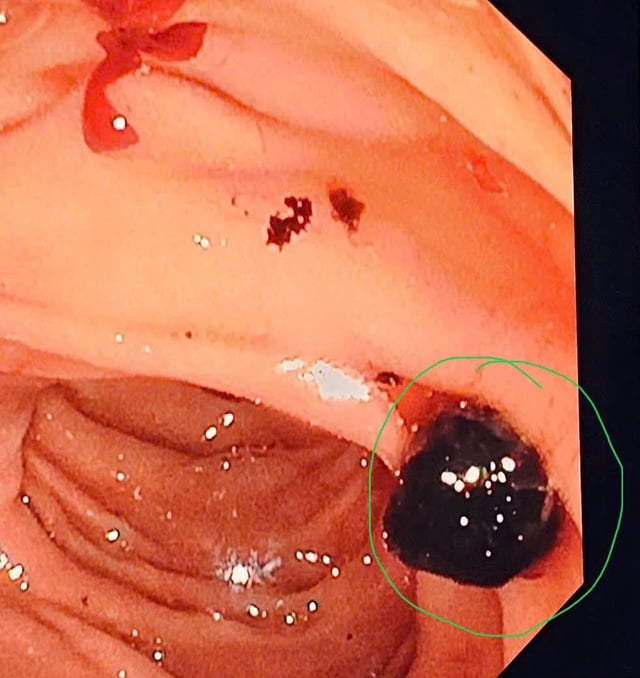

Obrázek kamene na obrazovce endoskopu.